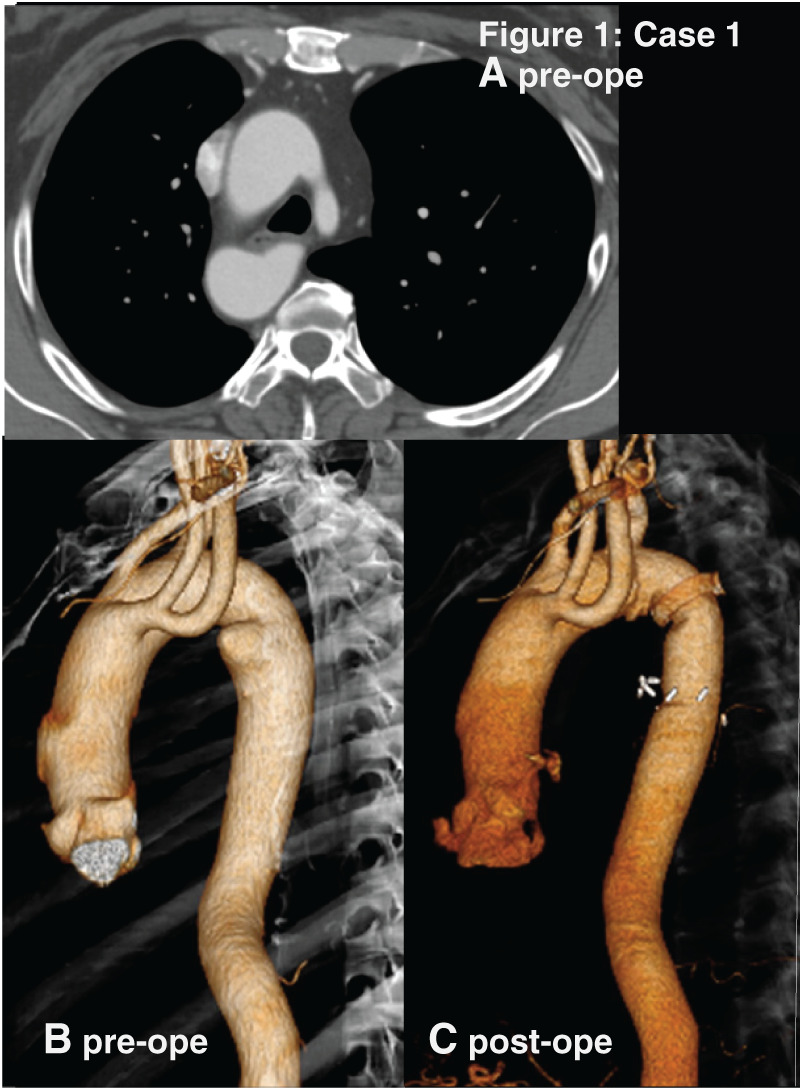

Case presentation: Four patients with right-sided aortic arch underwent different surgeries for Kommerell's diverticulum. The pattern of aortic arch was a mirror-image of the normal left aortic arch in Cases 1 and 2. In Cases 3 and 4, it was right-sided aortic arch with an aberrant left subclavian artery as its last branch. Cases 1 and 3 presented with compression symptoms caused by Kommerell's diverticulum. They underwent open surgery or thoracic endovascular aortic repair through the different approaches. Their postoperative courses were favorable.